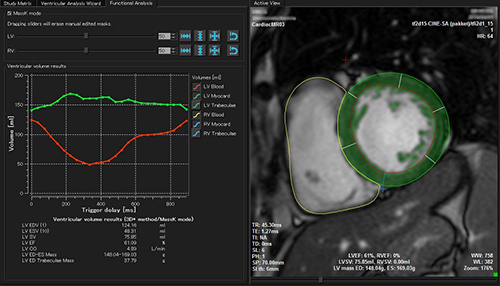

いずれも世界スタンダードといえる各種解析ソフトウェアの最新バージョンを取り揃えています。シネアンギオ解析のQAngio XAおよびCAASは定番の定量解析(QCA,QVA,LVA)を行います。心臓MR解析システムであるQMassESは一般的なシネMR解析や遅延造影解析,Perfusion解析に加え,T2強調画像からの浮腫定量化(Massk Mode),心筋サルベージの計算,T1・T2・T2*マッピング等の解析ツールを備えました。IVUS解析のQIvusでは,一般的なGrayscale解析,Tissue Characterization解析,OCT像のstent解析に加え,新しくNIRS解析も加えられました。また心エコー解析として有名なTomTec-Arenaも,各種4D解析がリニューアルされました。これら各種臨床研究ツールはGoodnetからシームレスに起動(※QMassESを除く)され,蓄積された画像データをストレスなく解析できます。

QMassES Massk Mode